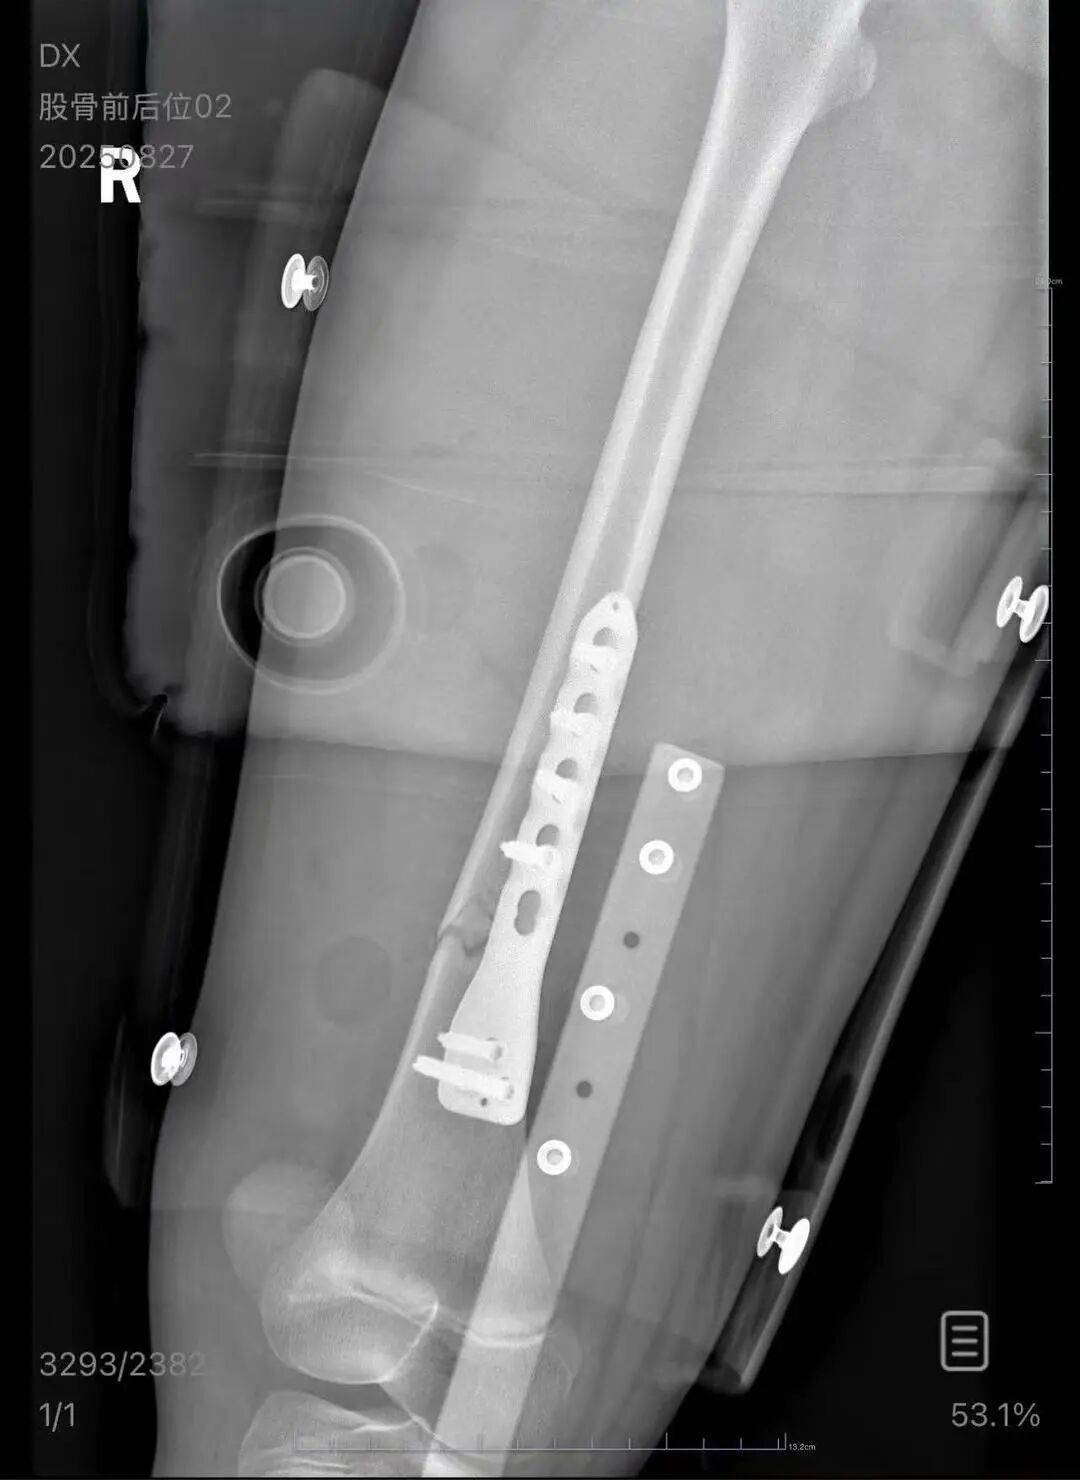

▲朱女士女儿手术后拍的X光片 受访者供图

朱女士出示的报警回执显示,8月24日凌晨2点22分,上海铁路公安处无锡站派出所接到报案私人挖虚拟币。报案人称,在某列车上,快要到无锡站时,上铺的乘客下床时没抓稳,导致孩子大腿骨折。

朱女士向记者出示的医院病历显示,8月24日凌晨,朱女士的女儿到医院就诊私人挖虚拟币。医院诊断朱女士的女儿右股骨骨折,需要住院进一步治疗。